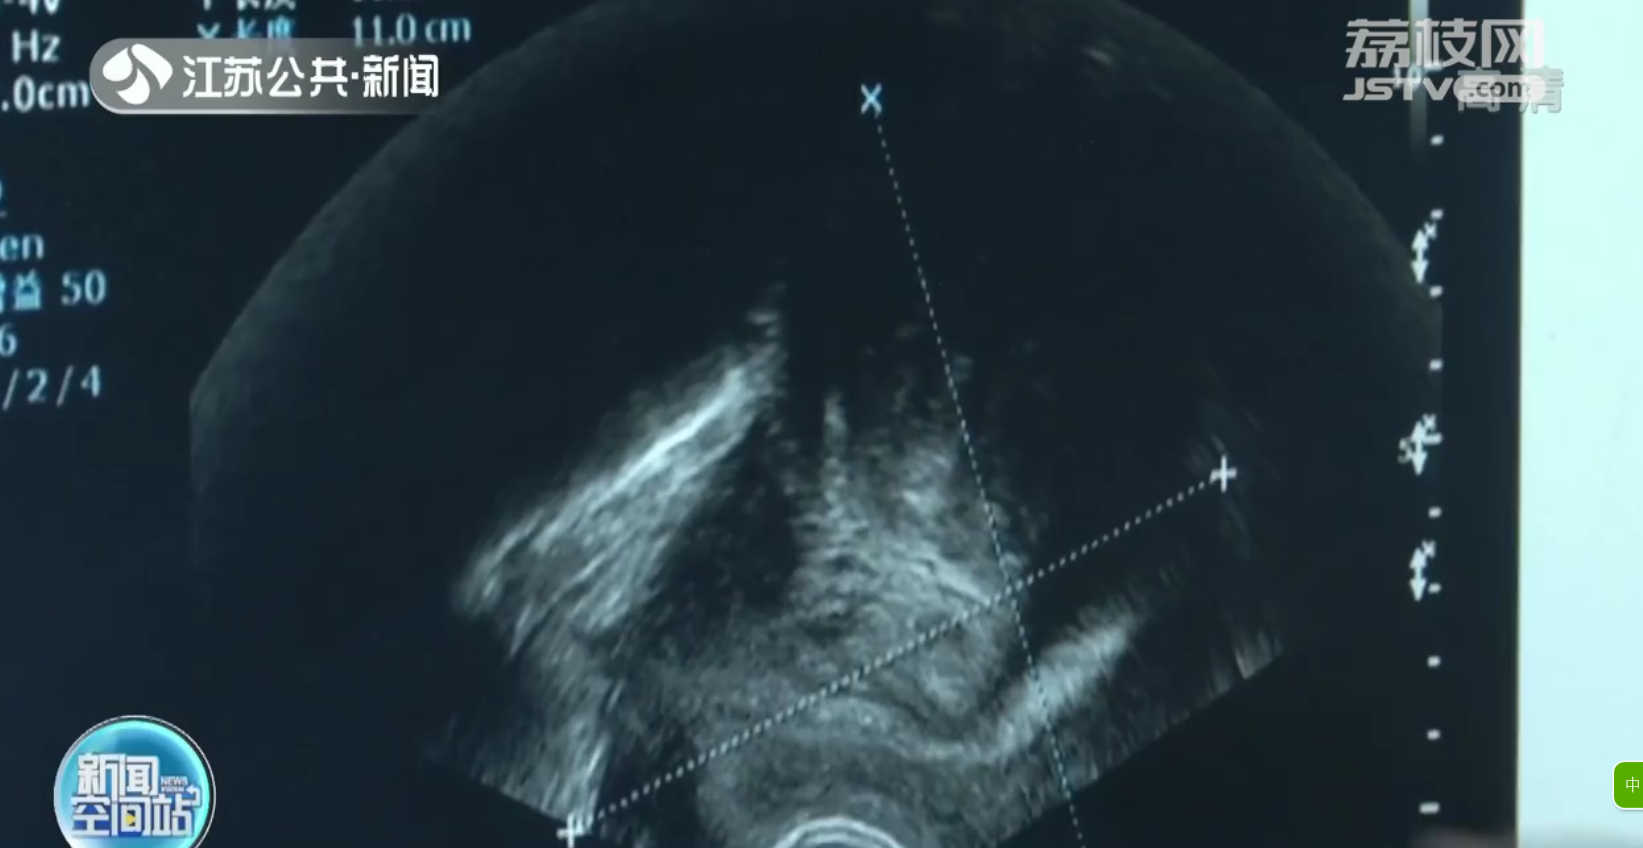

到医院检查后发现,患者的子宫肌瘤已经非常大,直径达到15厘米。

江苏省中西医结合医院妇产科副主任黄美华:“子宫的上界已经到肚脐下一到两指,也就是和我们正常怀孕大概四五个月那么大了,没有微创手术的条件,只能是开腹手术。”